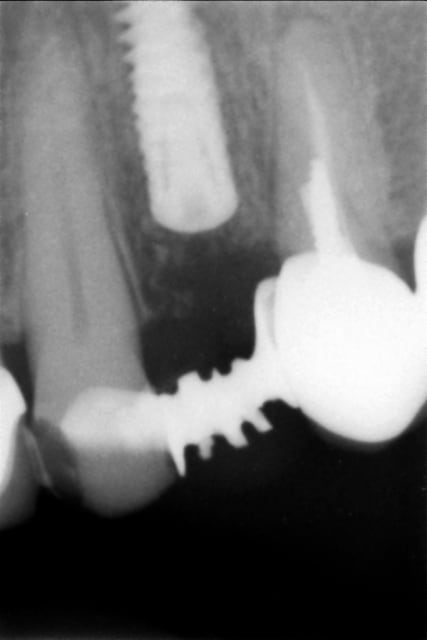

Alors voilà le premier cas :

EII sur 24 du 16/09/10

Obtention d'une stabilité primaire, mais plutôt fragile.

Temporisation par bridge Maryland collé sur une couronne métal en distal, ce qui a été la cause de multiple descellements, et possible traumatismes de l'implant via sa vis de cicat.

Manifestement une autre cause possible est la présence d'une infection maousse en dans le site le jour de la pose...

Qui dit la faute à Tekka ?